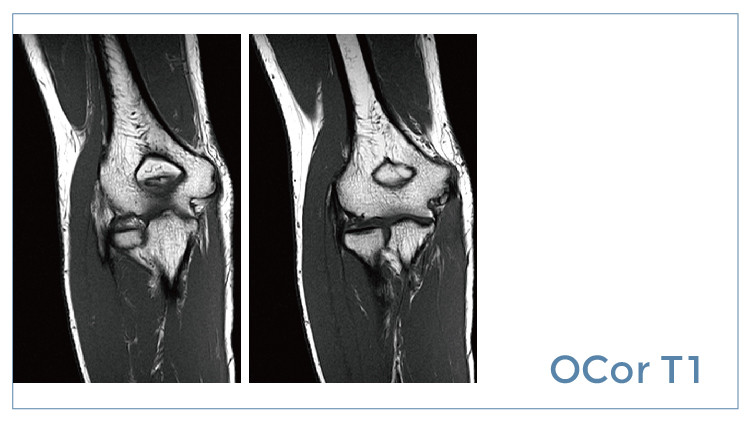

【朗润影像档案】20190726磁共振影像病例结果讨论